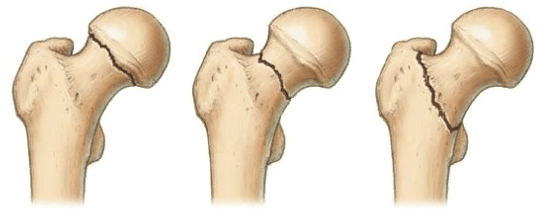

Локализация наиболее распространенных переломов.

- варусная деформация шейки;

- вальгус шейки бедра;

- псевдоартроз шейки бедренной кости; ;

- неправильно сросшийся перелом;